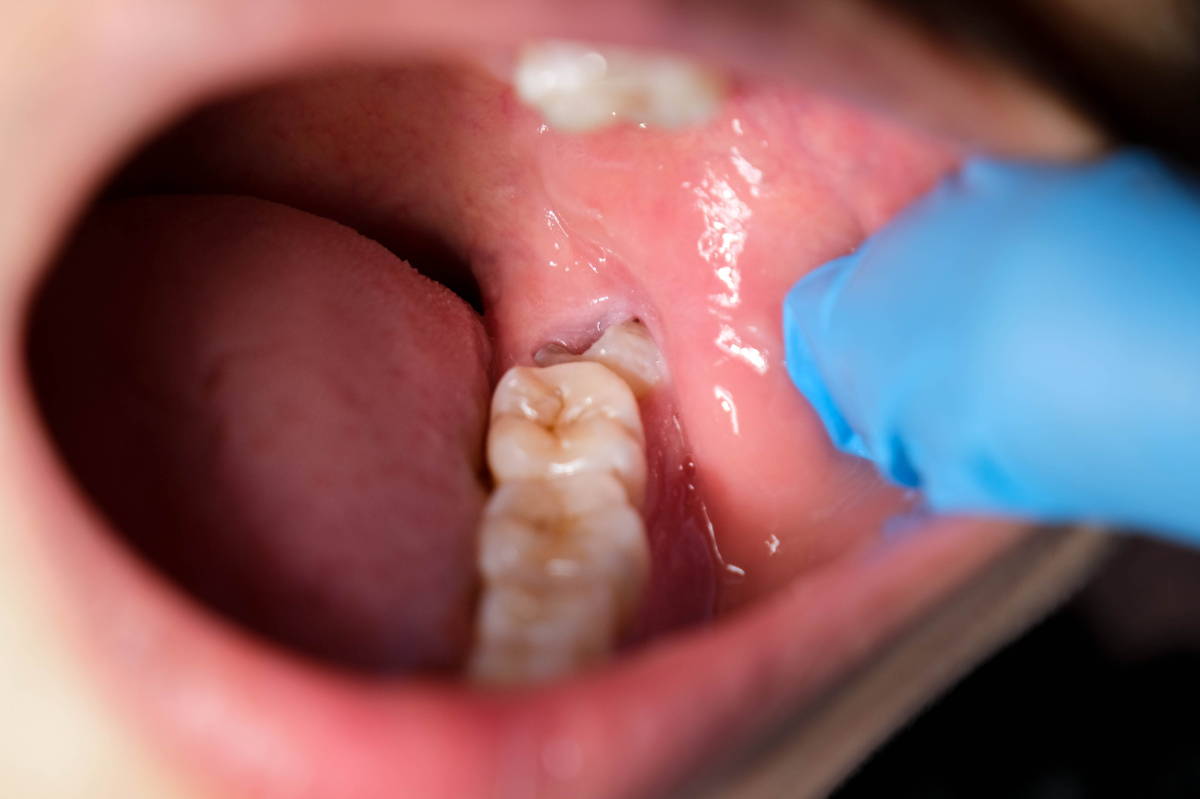

智歯周囲炎とは、親知らずの周囲に炎症が起こる状態で、一般的なトラブルのひとつです。多くの場合、親知らずが半分埋まったままの状態(半埋伏)で生えていて、歯と歯ぐきの間にできた隙間に細菌が侵入することで発症します。

初期段階では、親知らず周囲の歯ぐきが腫れたり軽い痛みを感じたりする程度ですが、炎症が進むと激しい痛みが出ることもあります。痛みだけではなく、膿や口臭、口が開けづらくなる開口障害などの症状が現れることもあります。

親知らずは歯列の一番奥にあるため、歯ブラシが届きにくく、汚れが溜まりやすい場所です。斜めに生えていたり一部だけ歯ぐきに覆われていたりすると、歯と歯ぐきのすき間に細菌がたまりやすくなります。その結果、親知らず自体が虫歯や歯ぐきの炎症を起こすリスクが高まります。